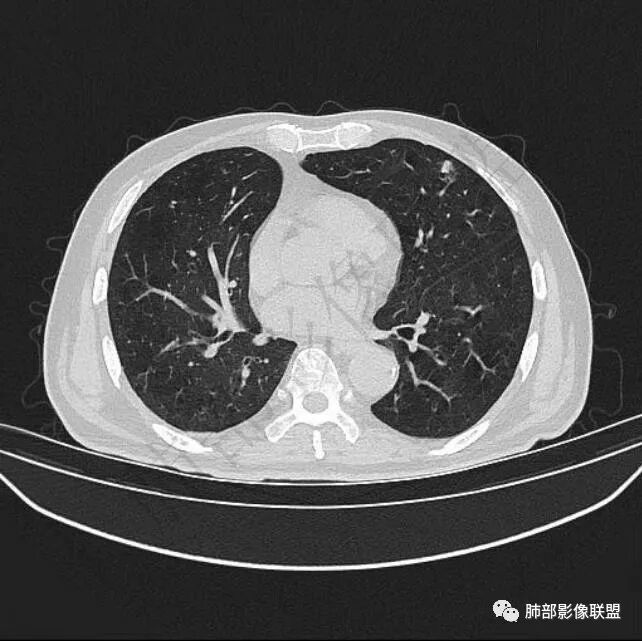

9个月后病灶明显增大,边缘较平直,部分膨隆,锁扣样外观,仍旧缺乏典型深分叶及张力,未见胸膜凹陷。

再1个多月后病灶继续增大,较明显不均匀强化,肺门一侧见低密度区。病灶边缘相对不清,可见毛刺。

三.病程脉络相当清楚,即病灶进行性增大,易想到新生物或转移瘤,但经验上分析增长速度显然太快,尤其是对于原发肺腺癌或者肺鳞癌而言,单发转移瘤也较少这样的进展速度。